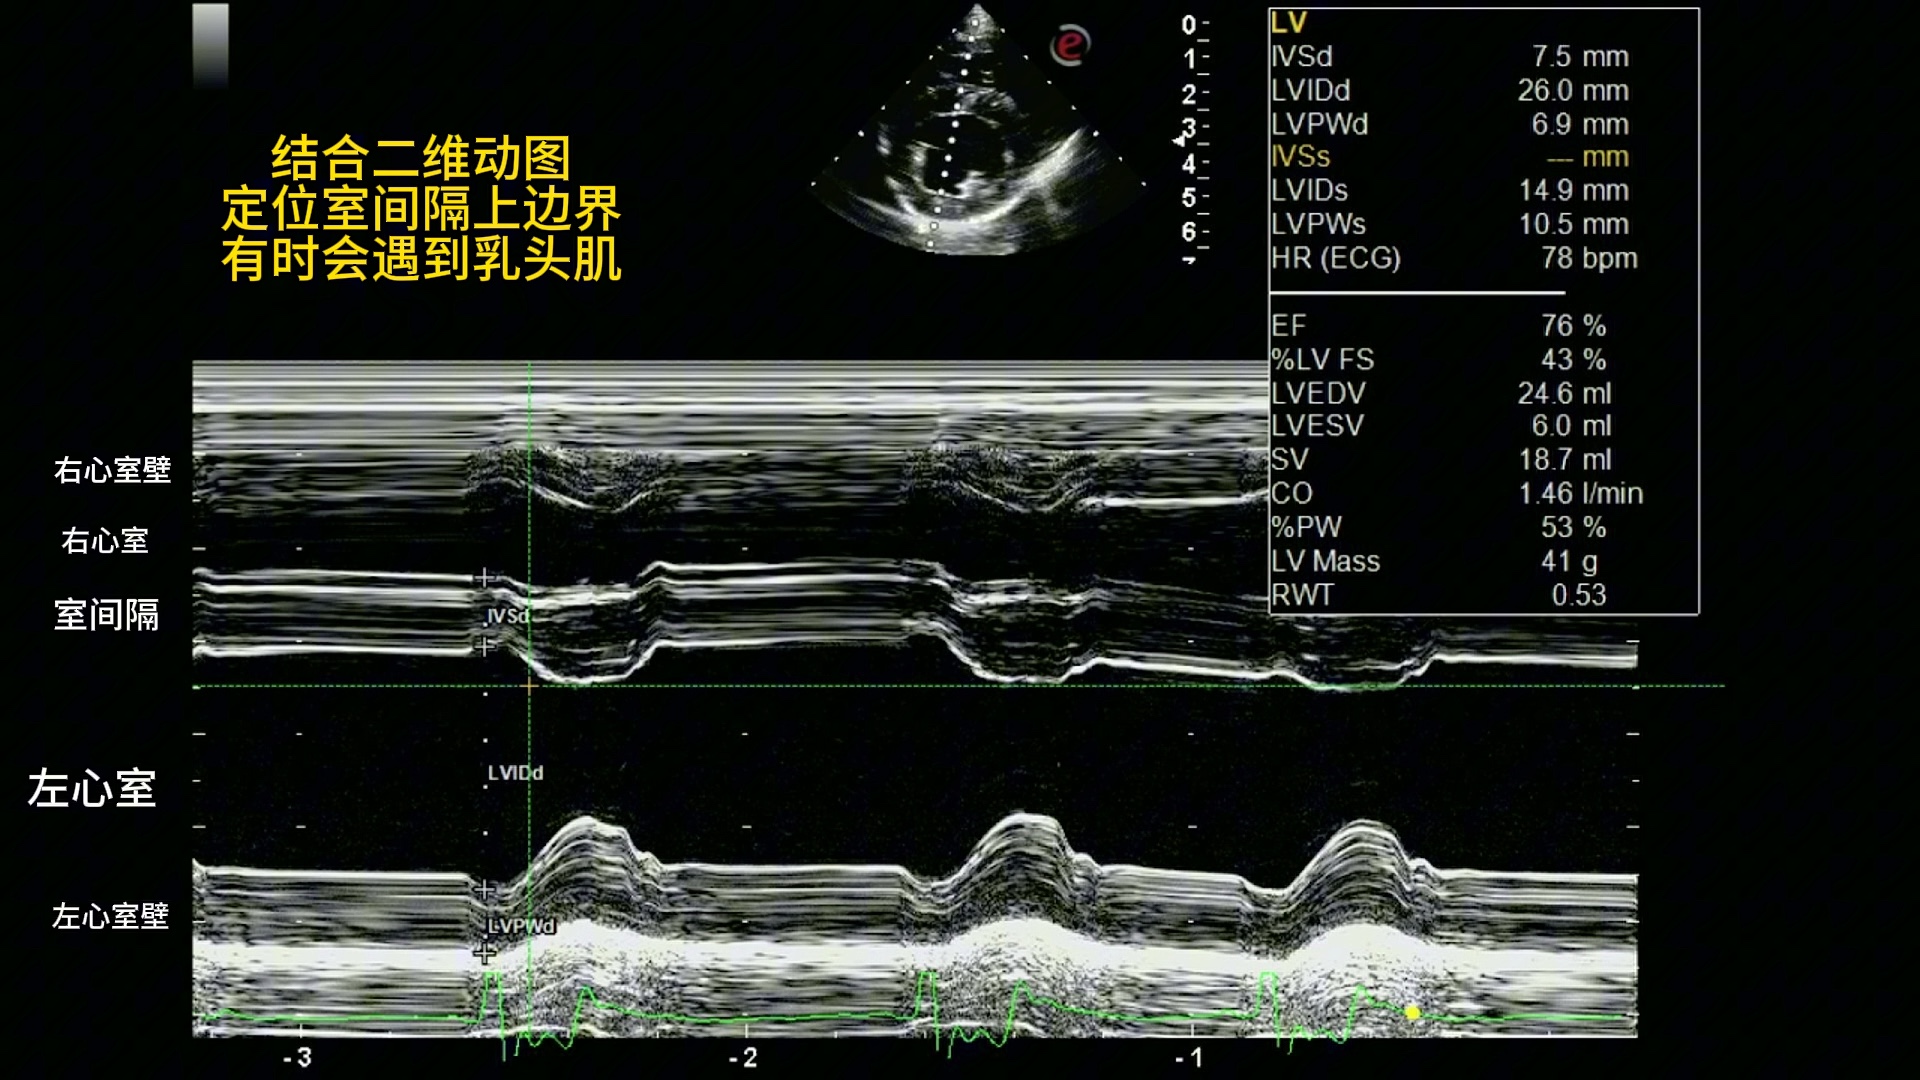

犬左心室M超测量。心脏超声。小动物心脏超声,